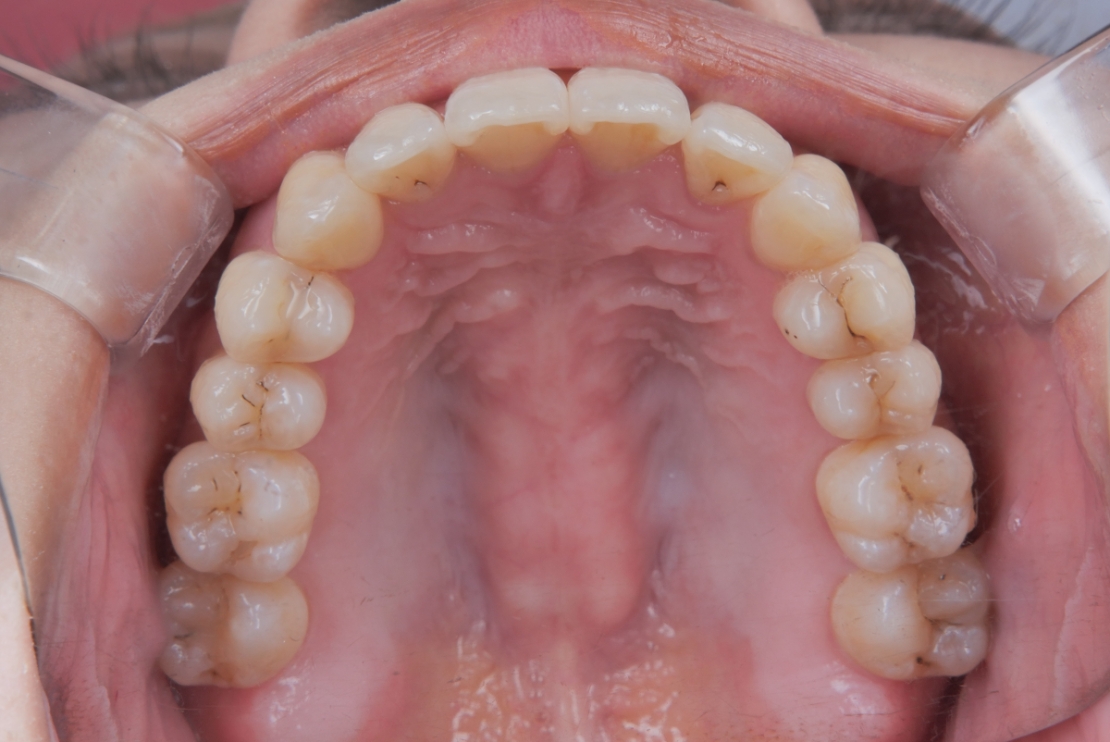

BEFORE

AFTER

| 施術内容 | 歯全体のマウスピース矯正システム「インビザラインフル」を用いた治療 |

| 治療期間 | 2年 |

| 費用 | 924,000円(税込) |